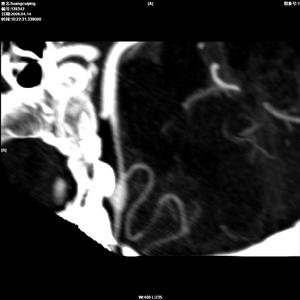

嗅覺障礙--造影②預防感冒,不長期使用某些藥物如四環素、鏈黴素、新黴素,不吸菸;